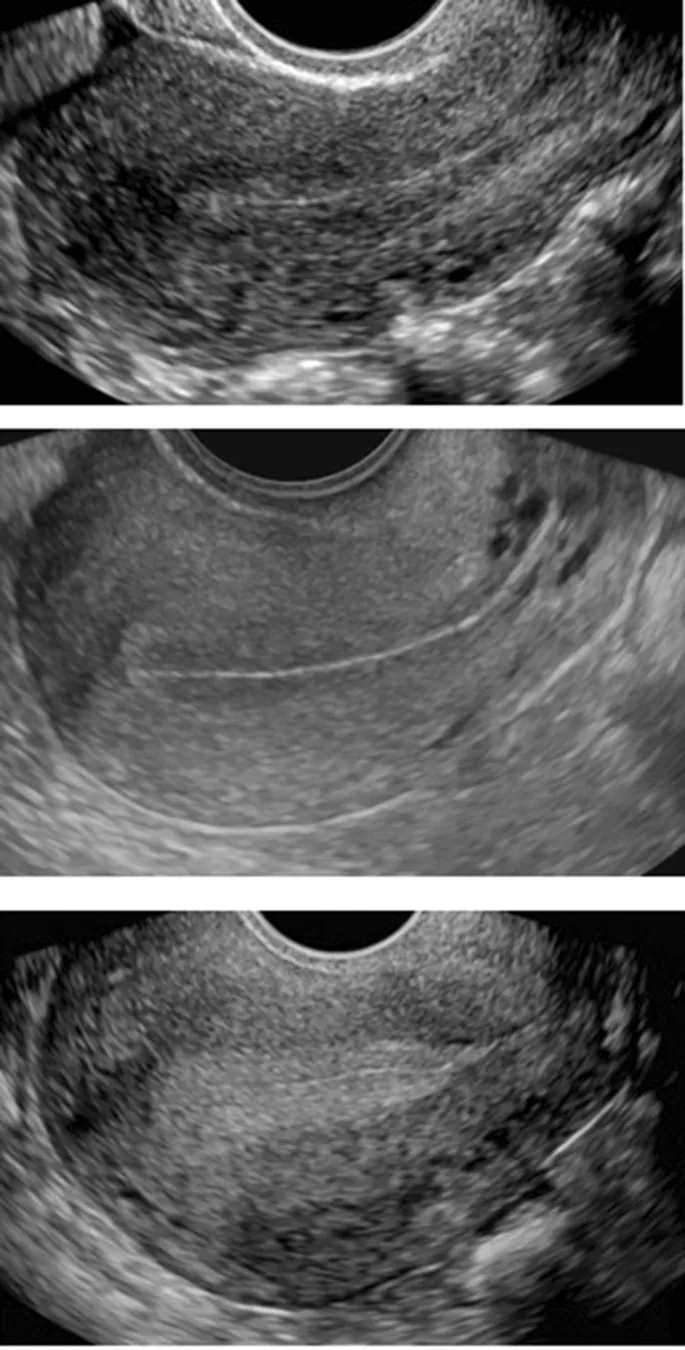

- TVUS: Initial modality for most female pelvic pathologies.

- Endometriomas: Unilocular cysts with homogenous low-level ("ground glass") echoes on US.